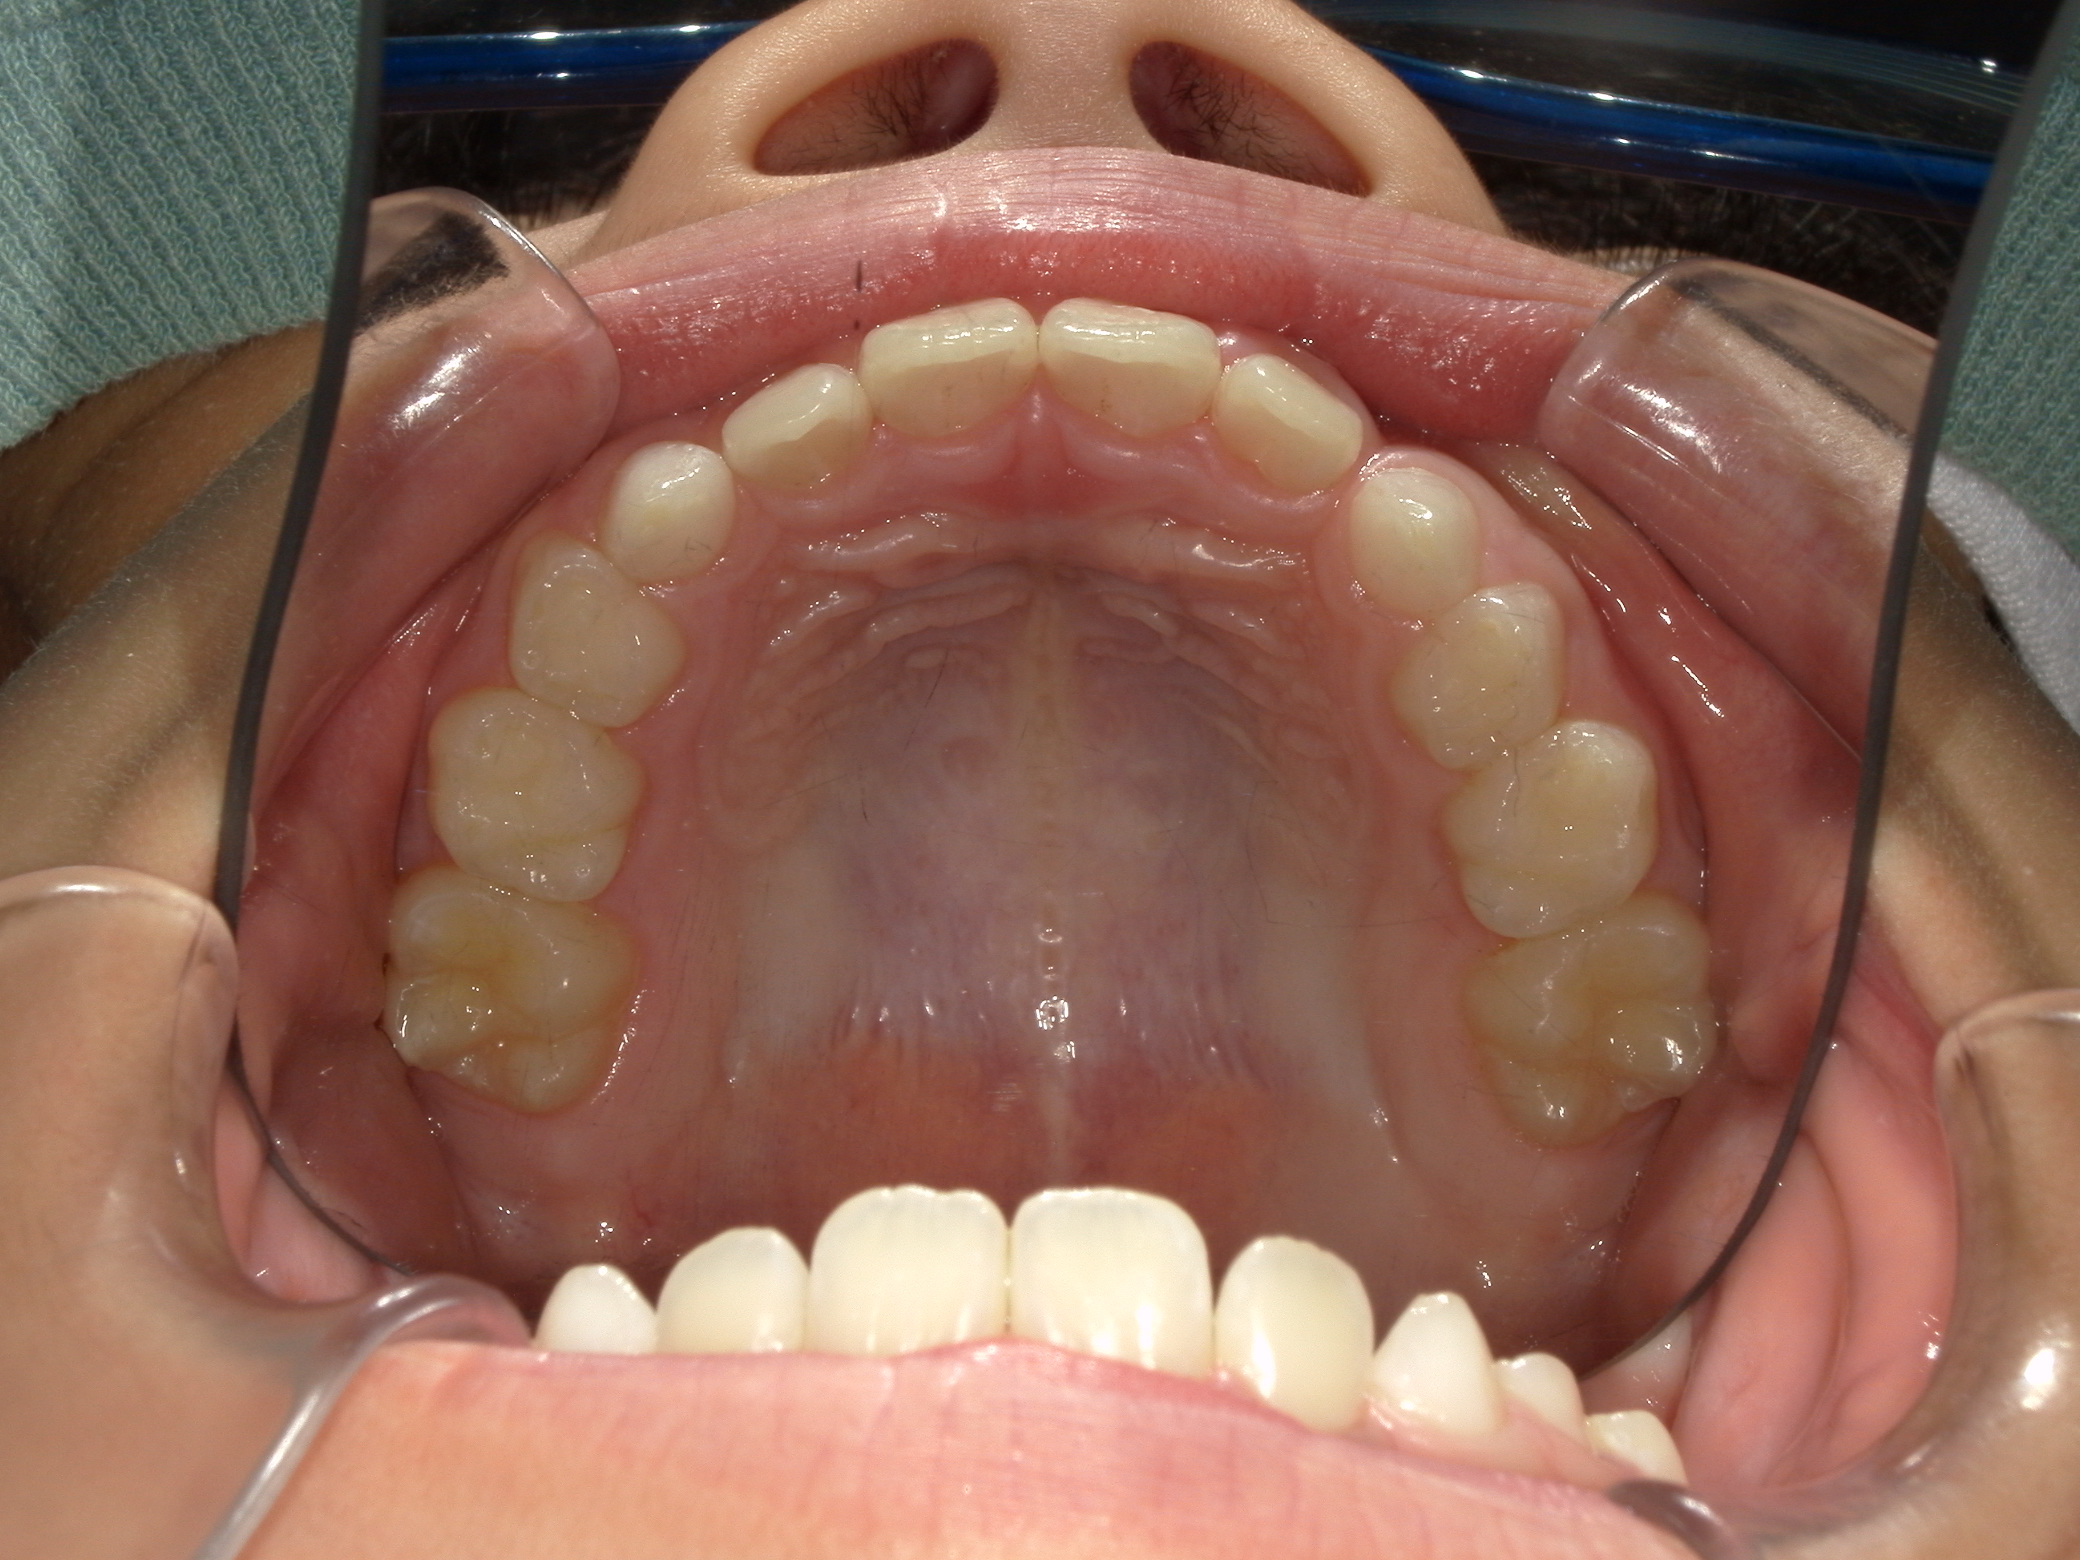

すきっ歯

7歳 女性

治療例前

プレオルソによる筋機能訓練(MFT)

筋機能トレーナー(プレオルソ)

495,000

約1年

舌癖による不正咬合が認められたため、プレオルソを使用して口腔周囲筋のバランスを整え歯並びが改善しました。

患者様の使用協力が得られれば、プレオルソのみで綺麗な歯並びにすることが可能です。歯の位置異常がないかなどのきちんとした矯正精密検査、矯正医の診断のもと装置の選択を行うことが大切です。

リスク:歯肉退縮、歯根吸収、後戻り、予期せぬ成長